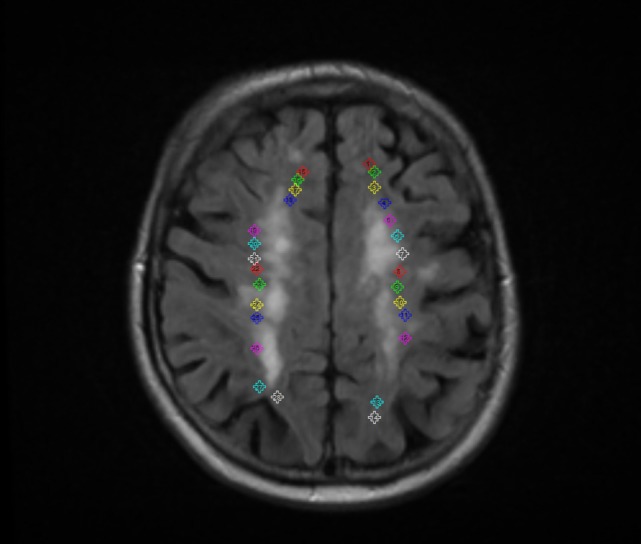

Case 3:

Refer to caption

Figure 4: Abdominal aorta, CT Scan taken as third case and its generated captions with respect of ground truth is given below:

• Ground Truth: Digital subtraction angiography confirming embolized patent foramen ovale occlusion device within abdominal aorta”

• Generated Caption:Digital angiography of the right artery and branches showing the proximal abdominal aorta”

Our model correctly identified the imaging technique as digital angiography” and accurately located the examination to the abdominal aorta.” The model demonstrated strong performance in modality recognition and the identification of the major anatomical structure, but revealed areas for improvement in the description of complex interventional devices and specific pathological processes.